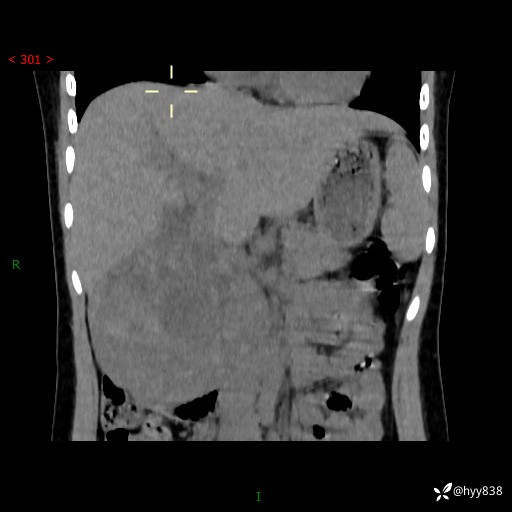

病例小姑娘,超声提示上腹部巨大包块。平扫就能轻松搞定的病变--结果公布

性别:女

年龄:13岁

简要病史:超声提示上腹部巨大包块

上腹部CT平扫

胰腺实性假乳头状瘤 (17)